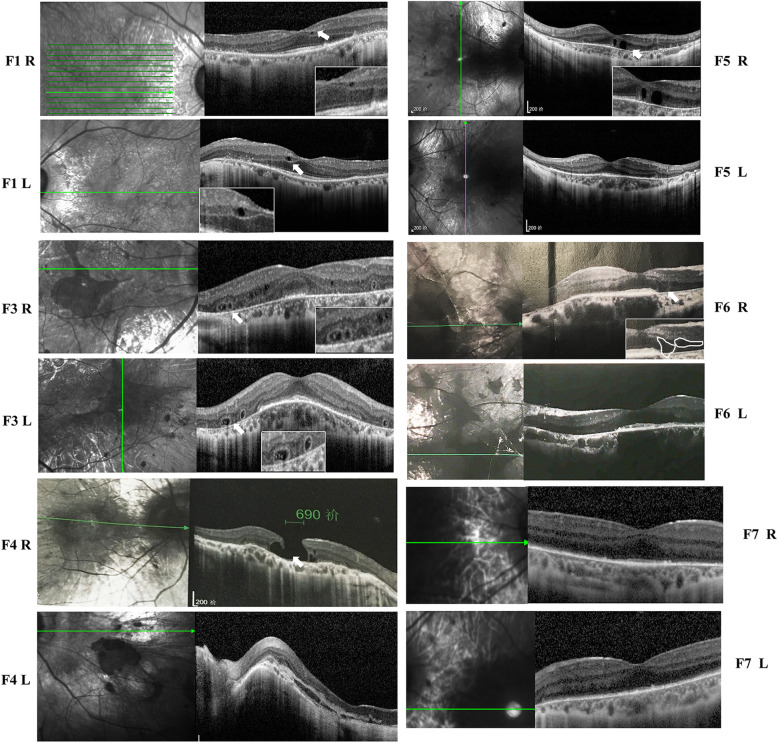

Analysis of the retinal structure using SD-OCT

Different degrees of RPE degeneration, CC and choroid atrophy were observed in the SC-OCT images from all patients (Fig. 3). In patient F1, the RPE had completely degenerated up to the posterior pole, with the preservation of the ellipsoid zone, the external limiting membrane, and the outer nuclear layer. A small cystoid space was observed in the inner nuclear layer of the retina of both eyes. In patients F3, F4, F5, and F6, multiple outer retinal tubulations were observed in the outer nuclear layer of the peripheral macula. OCT images of patient F4 showed the complete absence of the RPE layer, the CC and the choroid. A full-thickness macular hole was observed in the right eye, and the normal structure and morphology of the macula were disordered in the left eye.

Fig. 3.

OCT images of the six patients with choroideremia. White arrows: tubulations or cystoid spaces. R, right; L, left